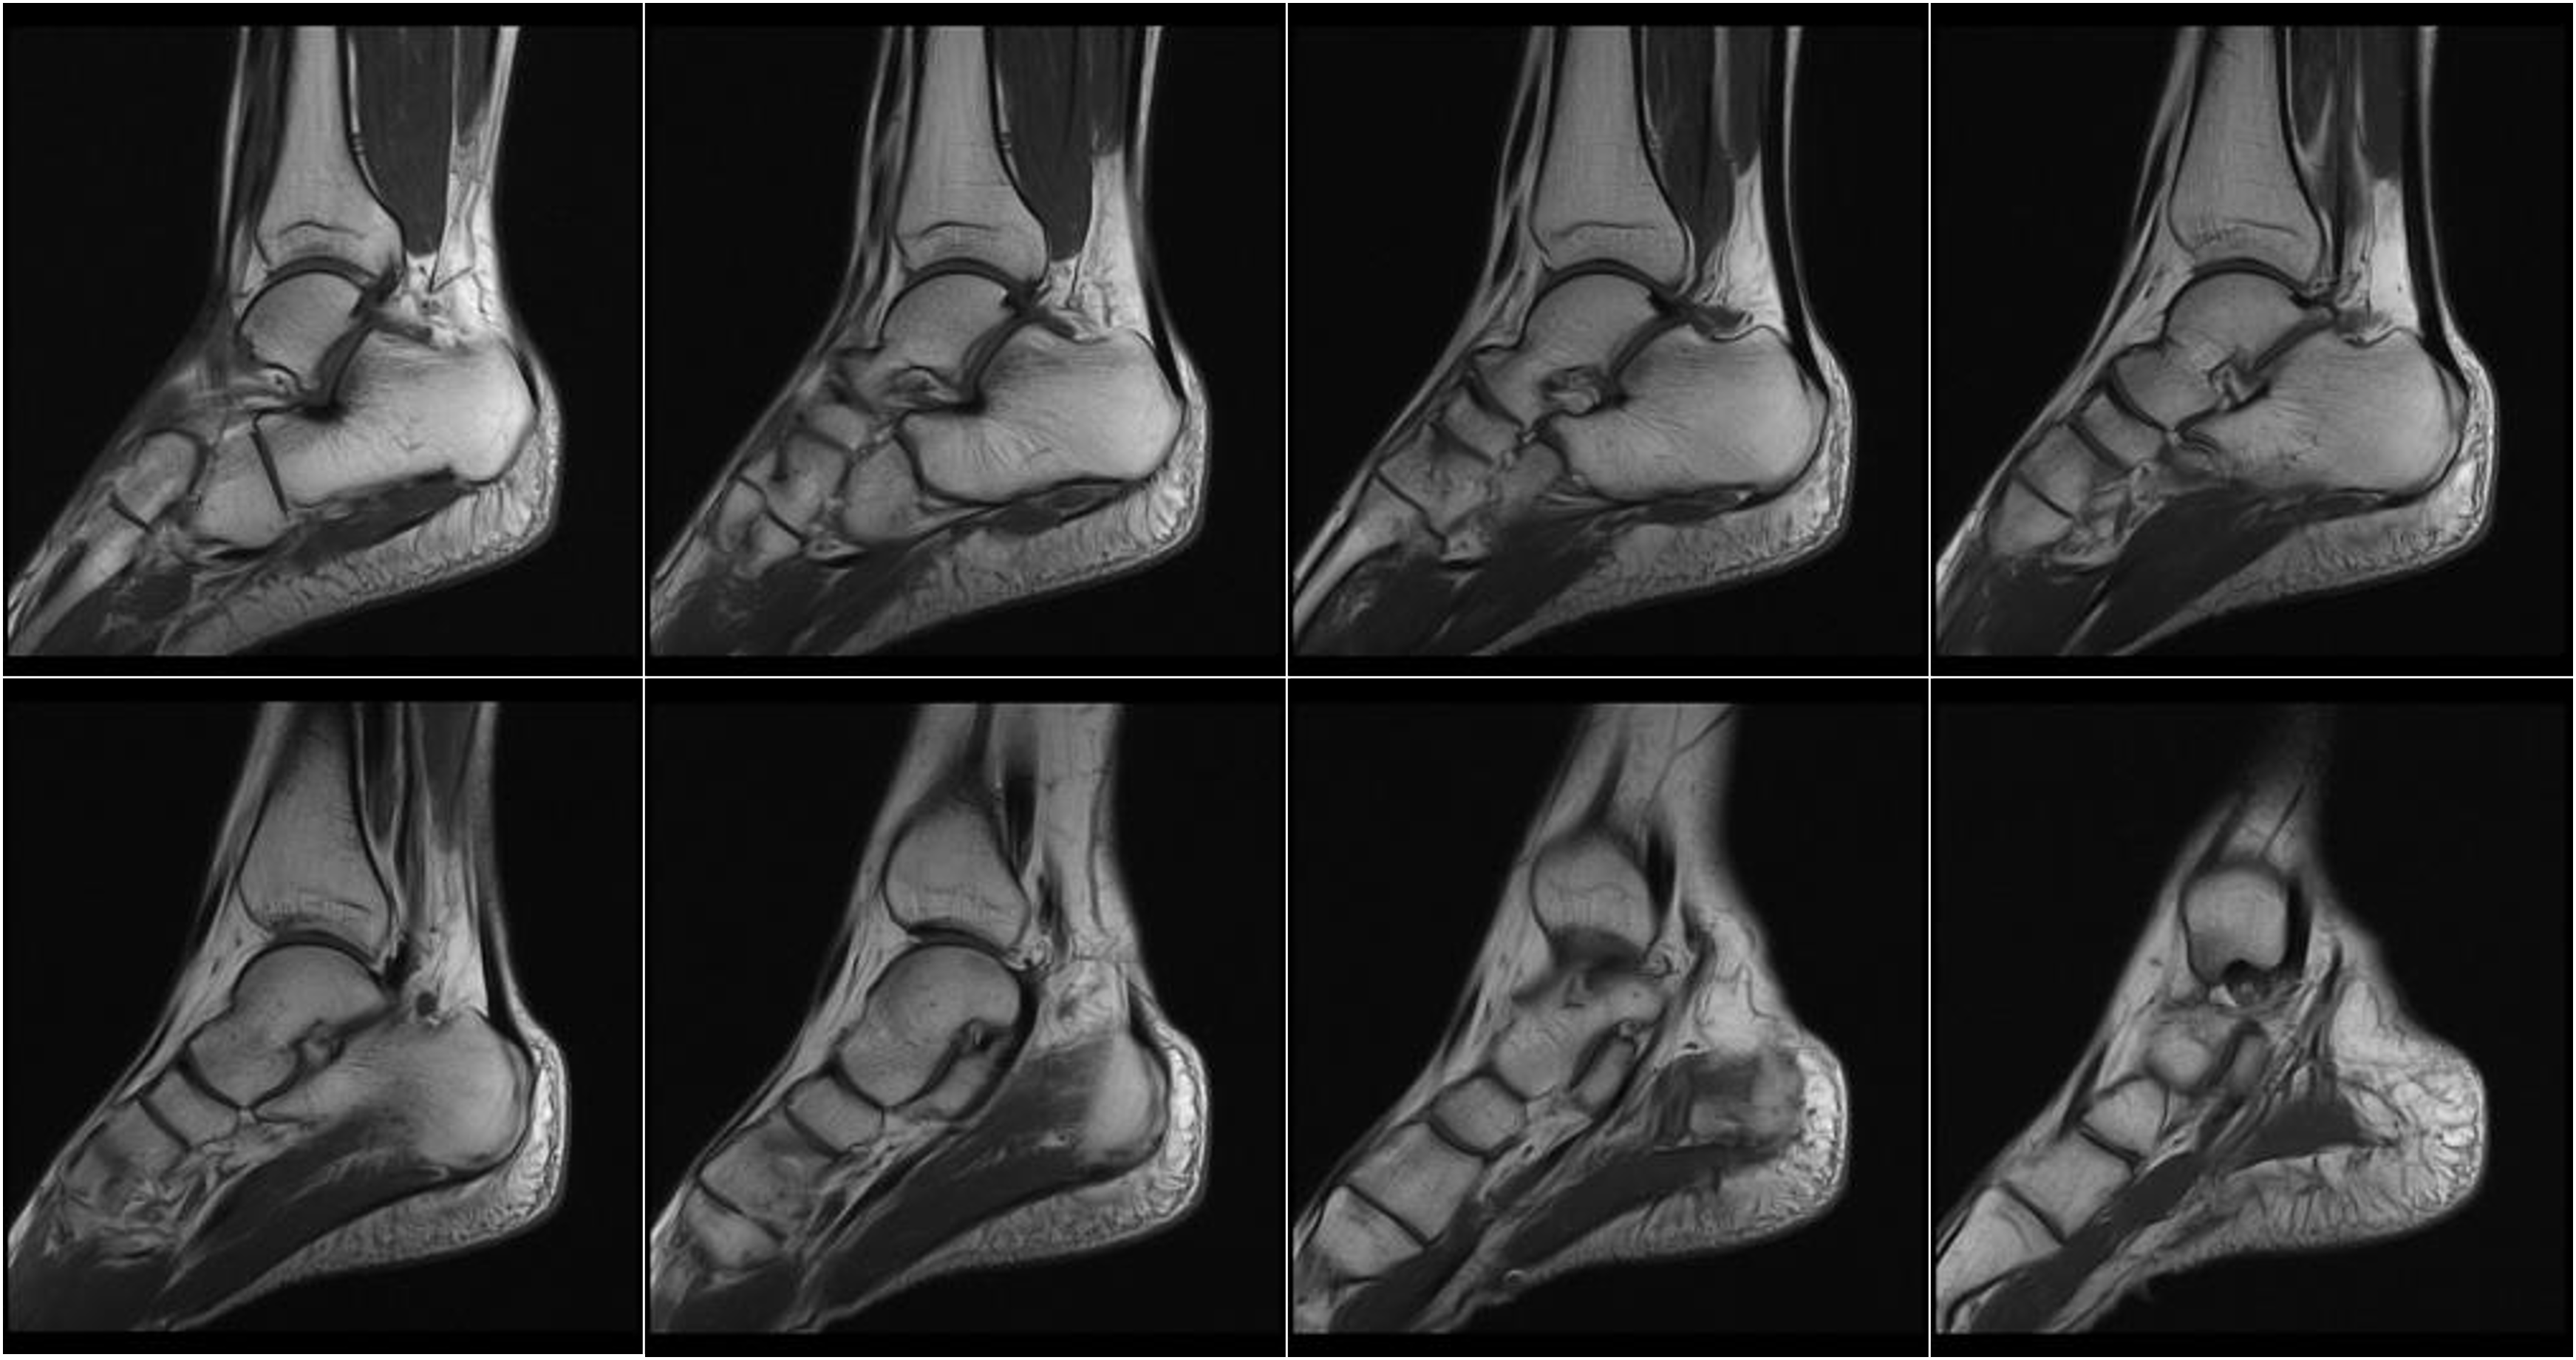

Hình ảnh lâm sàng